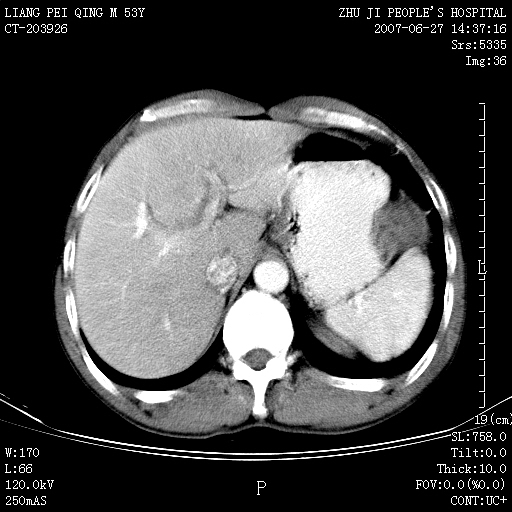

以下是引用余辉在2007-6-27 18:46:00的发言:[br]病灶多发,内可见大片状低密度区,病灶病灶等密度区轻度强化,动脉期后期病灶低密度区与高密度区对度增加,考虑1淋巴瘤2转移瘤3血管内皮细胞瘤(不知有否静脉期及延迟期扫描)

以下是引用zzzzhhhhaaaannnn在2007-6-27 20:44:00的发言:[br]脾脏 肋骨转移可能性大,下腔静脉内有癌栓

以下是引用狙击手在2007-6-28 10:35:00的发言:[br]1:定位:来源于脾脏。2:强化:强化,但不均匀。3:下腔静脉癌栓?下腔静脉充填不均匀与增强时间有关,延时即可明确。4:肋骨破坏?看起来并不确切。综上考虑几个最常见诊断:1;淋巴管瘤;2;血管内皮肉瘤(高度恶性,早期即可转移,常见肝,肺,骨)3;转移瘤(无特征性,只有肝或其它腹腔脏器有类似病变时,才可提示之)